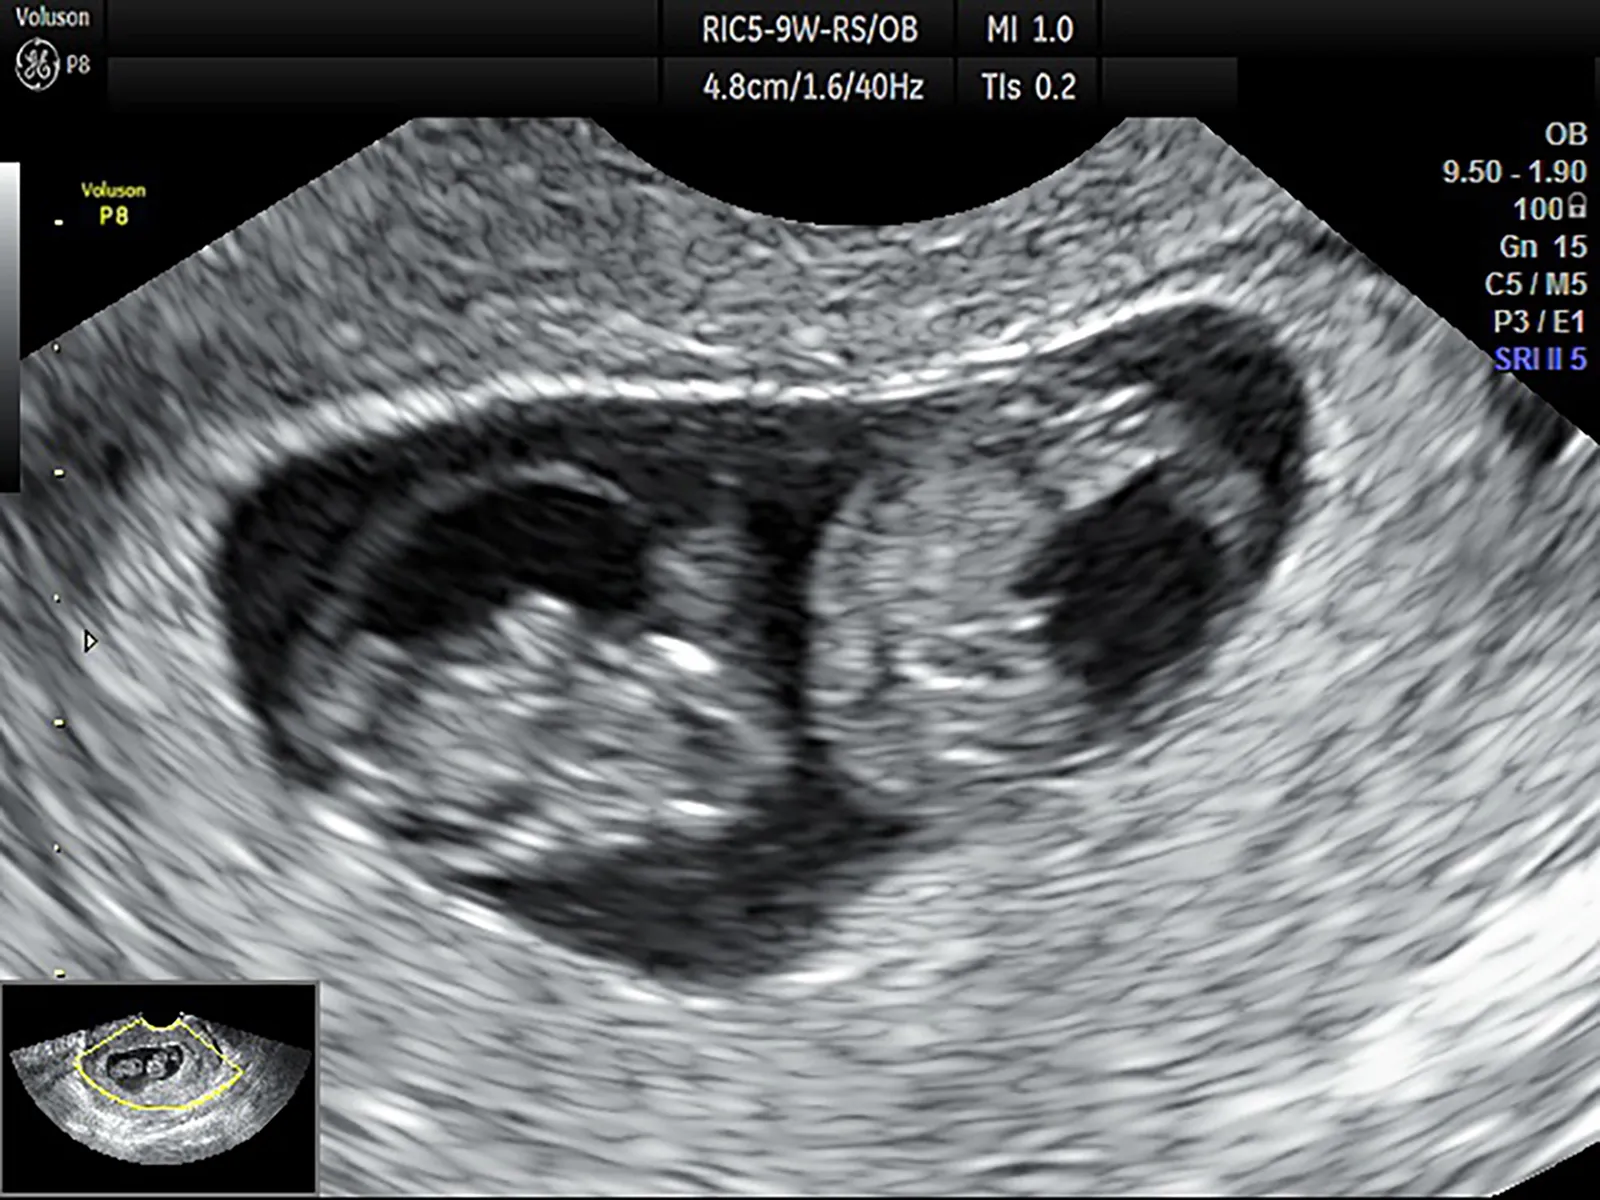

②-1 一絨毛膜二羊膜双胎(MD双胎)

胎児の部屋は分かれていますが、胎盤を共有しており、通常は1卵性です。

MD双胎